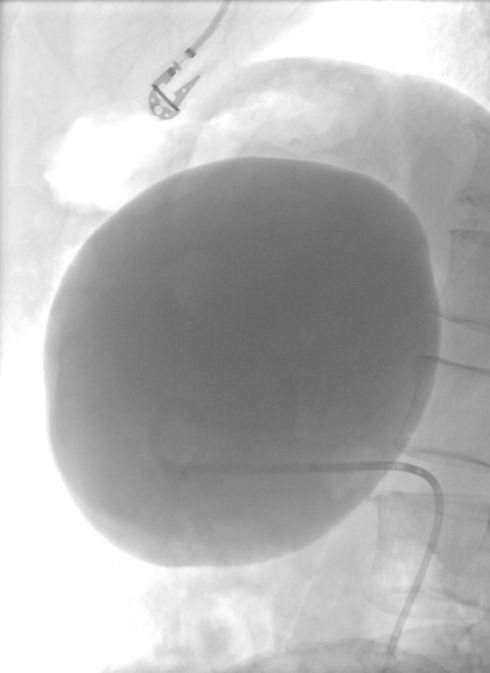

cisti renali e epatiche: trattamento mini-invasivo per cisti di grandi dimensioni

In presenza di sintomi o cisti di grandi dimensioni, è possibile trattarle in modo mini-invasivo mediante sclerotizzazione percutanea.

La procedura consiste nel pungere la cisti sotto guida ecografica, svuotarne il contenuto liquido e successivamente iniettare un agente sclerosante all’interno della cavità.

Questo trattamento consente di prevenire la recidiva, ridurre il volume della cisti e ottenere una regressione dei sintomi in tempi rapidi.